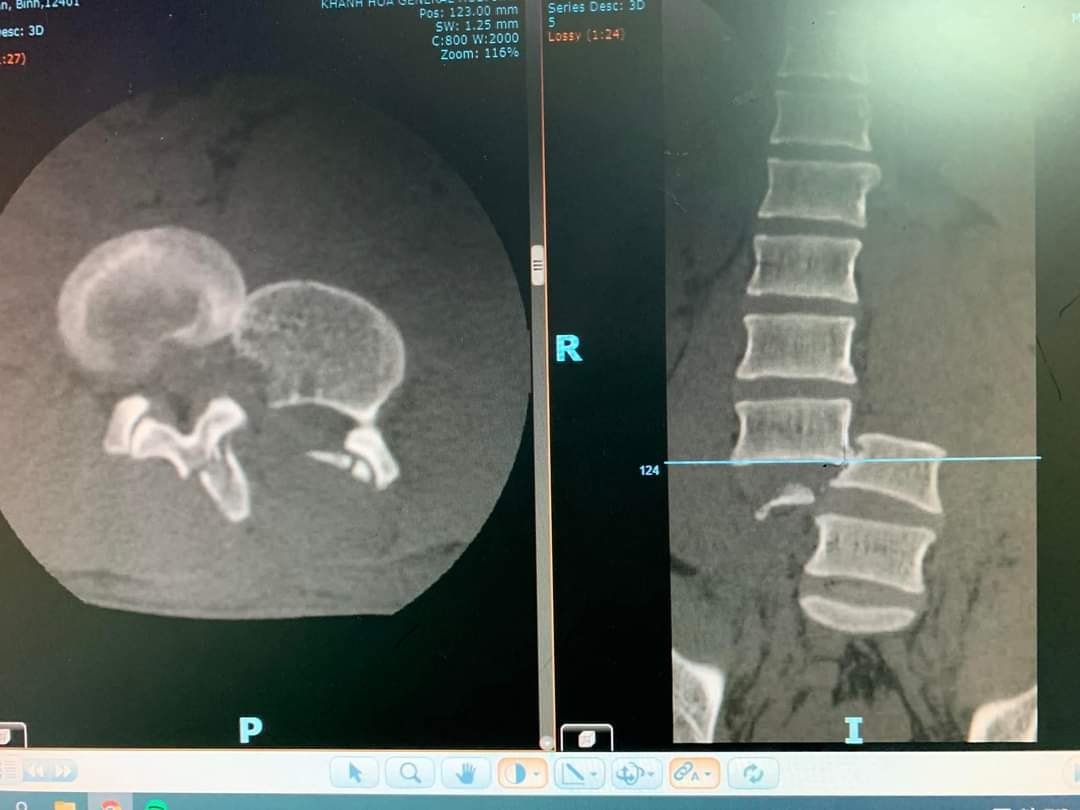

Kết quả CT – Scanner của bệnh nhân cho thấy có ít dịch ổ bụng, cơ thắt lưng chậu trái phù nề, tụ dịch chung quanh, tụ khí mô mềm hông lưng trái, dịch len lỏi giữa các cơ vùng lưng 2 bên. Gãy di lệch đốt sống L3 - L4 chèn ép tủy sống vùng này. Gãy mỏm ngang hai bên L5; gãy mỏm ngang hai bên, mỏm gai và thân đốt sống L4; mỏm ngang bên trái, mỏm gai và thân đốt sống L3. Gãy xương cánh chậu trái.

Hình ảnh chụp CT cột sống của bệnh nhân.

Các bác sĩ xác định bệnh nhân gãy trật di lệch ngang L3 - L4, gãy chân cung và mấu khớp L3 L4 L5, tổn thương thần kinh liệt hai chi dưới. Sau đó, bệnh nhân được phẫu thuật lúc 9g30 ngày 16/3.